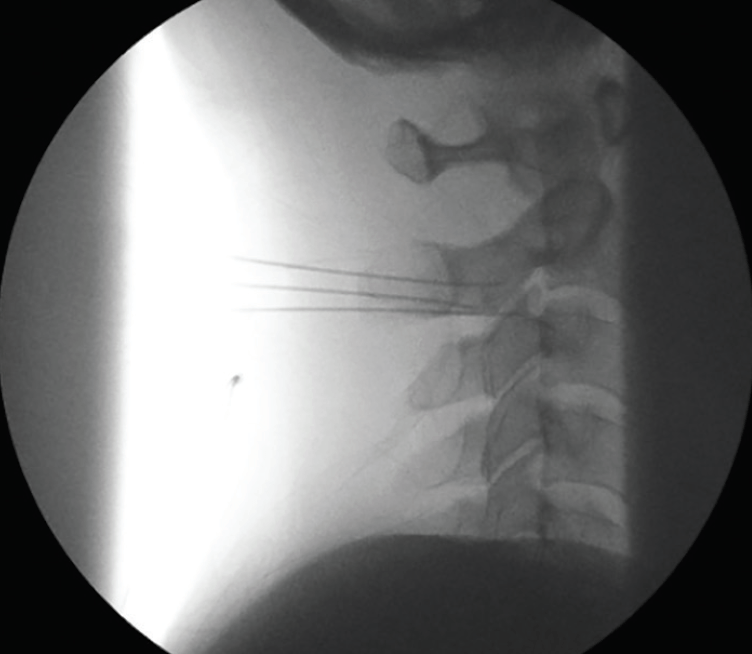

Third Occipital Nerve Block Blumenfeld Occipital Nerve Block Occipital and trigeminal nerve blocks for migraine. The occipital nerve block involves the injection of a local anesthetic and possibly a corticosteroid near the occipital nerves at the. The most widely used target for pnbs is the greater occipital nerve (gon). Andrew blumenfeld md, avi ashkenazi md, randolph w. Pnbs described include greater occipital, lesser occipital, supratrochlear, supraorbital, and auriculotemporal. Blumenfeld Occipital Nerve Block.

Third Occipital Nerve Block Blumenfeld Occipital Nerve Block Occipital and trigeminal nerve blocks for migraine. The most widely used target for pnbs is the greater occipital nerve (gon). Andrew blumenfeld md, avi ashkenazi md, randolph w. Other commonly targeted nerves are the lesser occipital nerve. The occipital nerve block involves the injection of a local anesthetic and possibly a corticosteroid near the occipital nerves at the. Pnbs described. Blumenfeld Occipital Nerve Block.

3rd Occipital Nerve Block Blumenfeld Occipital Nerve Block The most widely used target for pnbs is the greater occipital nerve (gon). Andrew blumenfeld md, avi ashkenazi md, randolph w. Occipital and trigeminal nerve blocks for migraine. Pnbs described include greater occipital, lesser occipital, supratrochlear, supraorbital, and auriculotemporal injections. Occipital and trigeminal nerve blocks for migraine. Other commonly targeted nerves are the lesser occipital nerve. The occipital nerve block. Blumenfeld Occipital Nerve Block.

Third Occipital Nerve Block Blumenfeld Occipital Nerve Block The most widely used target for pnbs is the greater occipital nerve (gon). Other commonly targeted nerves are the lesser occipital nerve. Objective to describe a standardized methodology for the performance of peripheral nerve blocks (pnbs) in the treatment. Occipital and trigeminal nerve blocks for migraine. Occipital and trigeminal nerve blocks for migraine. Andrew blumenfeld md, avi ashkenazi md, randolph. Blumenfeld Occipital Nerve Block.